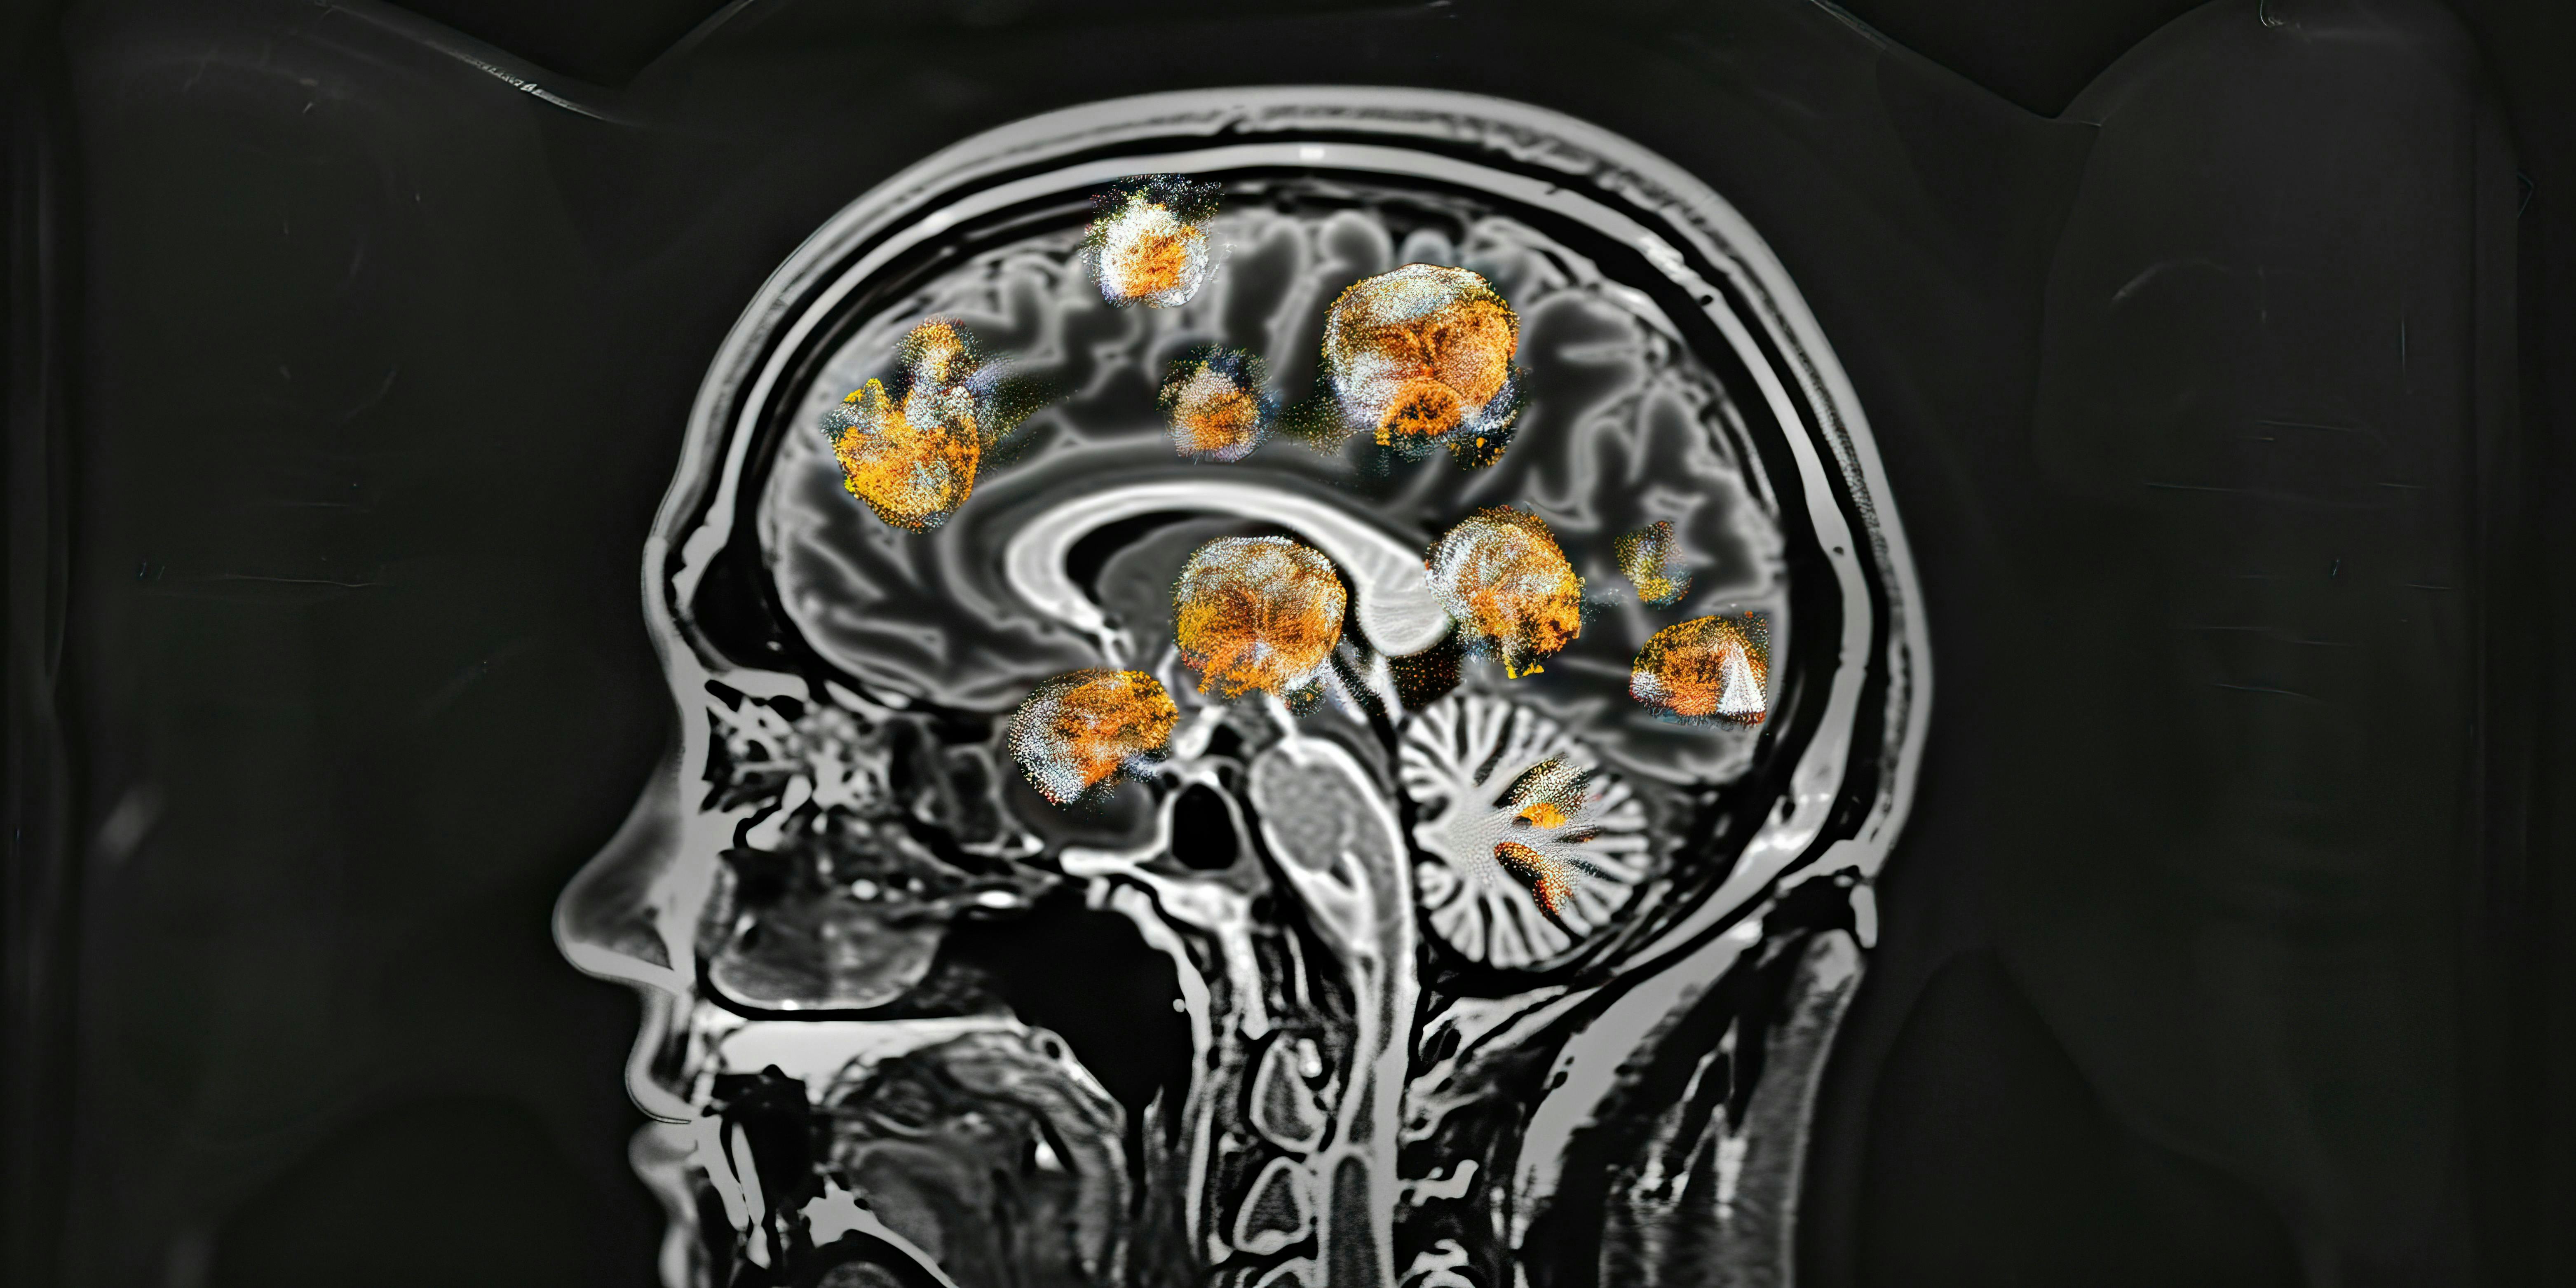

MLO LABline Daily - Jan 29th, 2026